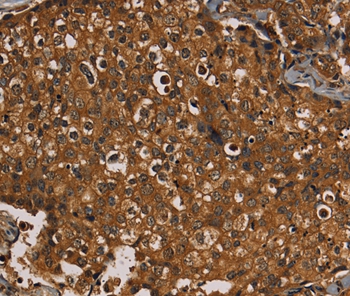

Immunohistochemical analysis of paraffin-embedded Human thyroid cancer tissue using #36571 at dilution 1/20.